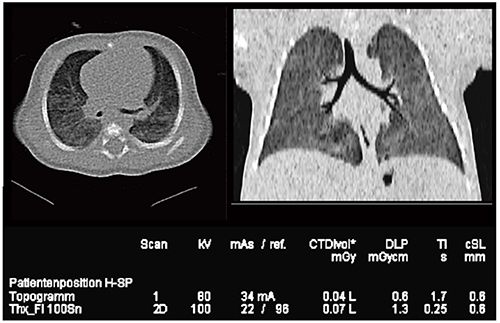

Case11は生後32日の新生児で,検査中に泣いていたが,わずか0.1秒の撮影のため体動アーチファクトは見られない。加えて,DLP 1.3mGy・cmと非常に低い被ばく線量を達成しつつ,画質はきわめて良好である(図18)。

図18 Case11:70kVのSedation Free CT(生後32日,新生児)